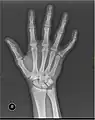

X-ray

X-ray image of right hand with thumb on left.

Multiple fractures of the metacarpals (aka broken hand). (Right hand shown with thumb on left.)